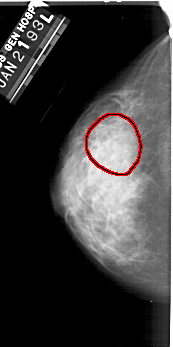

A_1353_1.LEFT_MLO

LEFT_MLO LINES 5446 PIXELS_PER_LINE 2896 BITS_PER_PIXEL 12 RESOLUTION 43.5 OVERLAY

FILE: A_1353_1.LEFT_MLO.OVERLAY

TOTAL_ABNORMALITIES 1

ABNORMALITY 1

LESION_TYPE CALCIFICATION TYPE PLEOMORPHIC DISTRIBUTION SEGMENTAL

ASSESSMENT 4

SUBTLETY 2

PATHOLOGY BENIGN

TOTAL_OUTLINES 1

BOUNDARY